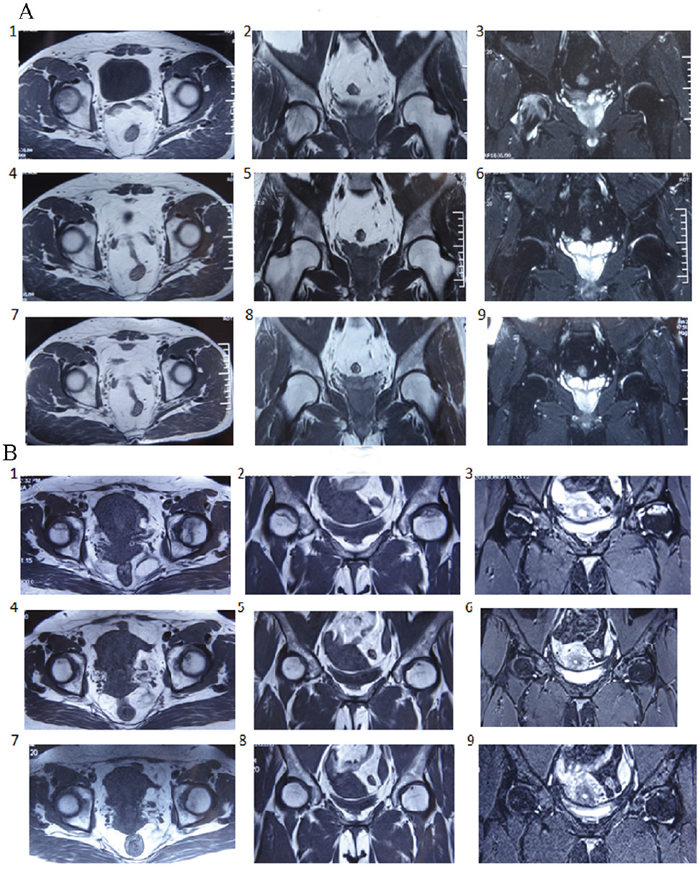

We evaluated the efficacy of BSP in patients with avascular necrosis of the femoral head using a double-blind, randomized controlled trial. A total of 300 ONFH patients were included in this study (Table 2A). Of these, 100 were salvia tablets were used as the control pills. The effective rate of BSP was 82%, which was significantly higher than that of the control pills (Table 2B). The rate of improvement in pain relief, hip joint function, and claudication was significantly better in the BSP group than in the control group (Table 2C–2F). Sex, age, or etiological subtypes had no effect on the response to BSP (Table 2G–2I). Representative cases are shown in Figure 3A and 3B. Moreover, BSP could significantly ameliorate ONFH as evaluated by X-ray analysis (Table 2J). The results from routine blood, urine, heart, liver, and kidney tests showed that BSP was safe, and BSP significantly ameliorated ONFH as evaluated by MRI analysis (Table 2K, Figure 4A and 4B).

Figure 4: Representative case of osteonecrosis of the femoral head (ONFH) evaluated by magnetic resonance imaging (MRI). (A) 54-year-old male patient, alcoholic (250 ml of alcohol per day). 1 - 3: There were abnormal signals on the right side of osteochondritis of the femoral head and an extensive area of abnormal signals under the perichondrium. 4 - 6: After treatment with the bone-strengthening pill (BSP) for 6 months, the abnormal signals disappeared and the patient resumed normal work. 7 - 9: The MRI image had no abnormalities at 1-year follow-up. (B) 49-year-old female patient, steroid administration 5 years ago and ONFH for 2 years. 1 - 3: MRI showed slight collapse of the bilateral femoral head. There were large and irregular long T1 and long T2 signals on the anterior superior segment of the bilateral femoral head. STIR revealed that the necrotic lesions exhibited a ladder-like, high, mixed, uneven abnormal signal, disappearance of cartilage signal especially on the left side. 4 - 6: The abnormal signals decreased and the patient could undertake light work after treatment for 6 months. 7 - 9: At 1-year follow up after treatment, the MRI was normal and patient could work as usual.